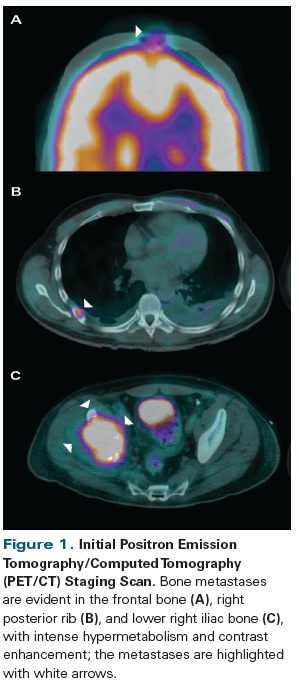

Figure 1: Initial Positron Emission Tomography/Computed Tomography (PET/CT) Staging Scan

A 42-year-old man presented with increasing right hip pain that limited his ability to walk. Magnetic resonance imaging (MRI) revealed a right lytic acetabular lesion. Further work-up included a computed tomography (CT) scan, which revealed an 8-cm left kidney tumor, and a positron emission tomography (PET)/CT scan (Figure 1), which showed osseous metastases involving the right acetabulum, the posterior end of the sixth right rib, and the cranium (frontal bone).